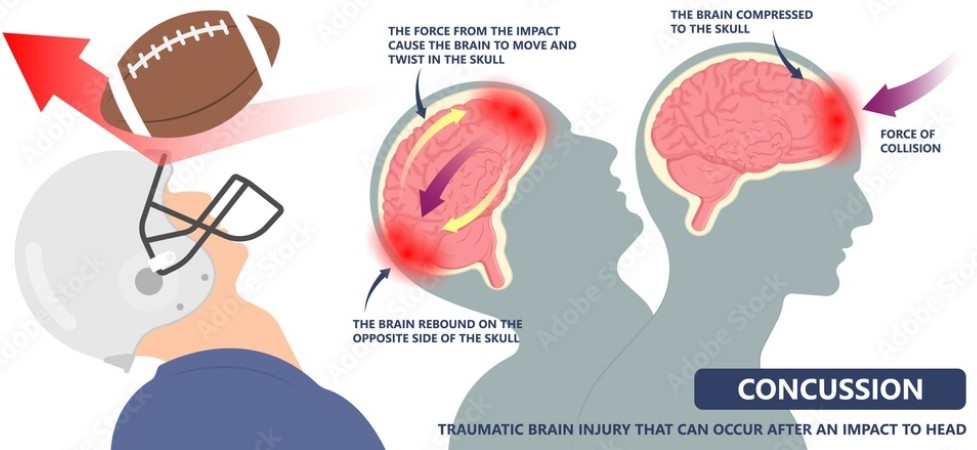

Sports-related head and neck trauma, including whiplash and concussions, often involves sudden neck extension or flexion, causing cervical disc damage or nerve pressure. Symptoms include neck pain, stiffness, headaches, dizziness, radiating arm pain/numbness, and concussion-related issues like memory problems or fatigue. These injuries impact athletic performance and daily life. At DRX Chicago, we provide comprehensive care for complex head and neck injuries to promote recovery, with thousands of athletes affected by concussions and whiplash annually.

Sudden forces in sports such as the jarring impact of a collision, the abruptness of a fall, or the swift, forceful movements required in athletic performance—can result in serious consequences for the cervical spine.

Sudden forces in sports such as the jarring impact of a collision, the abruptness of a fall, or the swift, forceful movements required in athletic performance—can result in serious consequences for the cervical spine.

These forces may lead to misalignment of the cervical vertebrae, injuries to the intervertebral discs, or irritation of nearby nerves, all of which can occur even without direct trauma to the head. Such injuries highlight the importance of proper technique, protective gear, and awareness of one’s surroundings during physical activity.

Forces encountered in sports, such as: impacts, falls, or sudden motions—can lead to misalignments in the cervical spine, disc injuries, or nerve irritation, even in the absence of direct head injury.